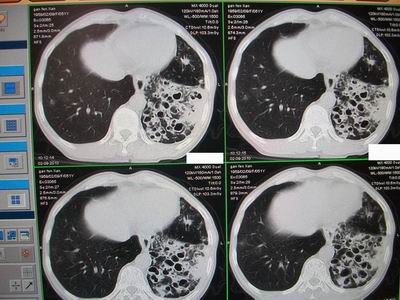

标题: CT24546:支气管扩张?多发性肺囊肿?请高手发表意见吧 [打印本页]

标题: CT24546:支气管扩张?多发性肺囊肿?请高手发表意见吧

临床:女性,51岁,一年来咳嗽、咳痰,反复发作,近两个月带少许血丝。

查体:精神较差,消瘦,余未见明显异常。

图片如下:\

“印戒征”,支扩伴感染

病变主要延肺动脉走形,多发囊状影较小且壁厚,还得先考虑---支扩伴感染。

支扩:腔小、壁厚、多液平;多发性肺囊肿:腔大、壁薄、少液平,本例符合支扩合并感染